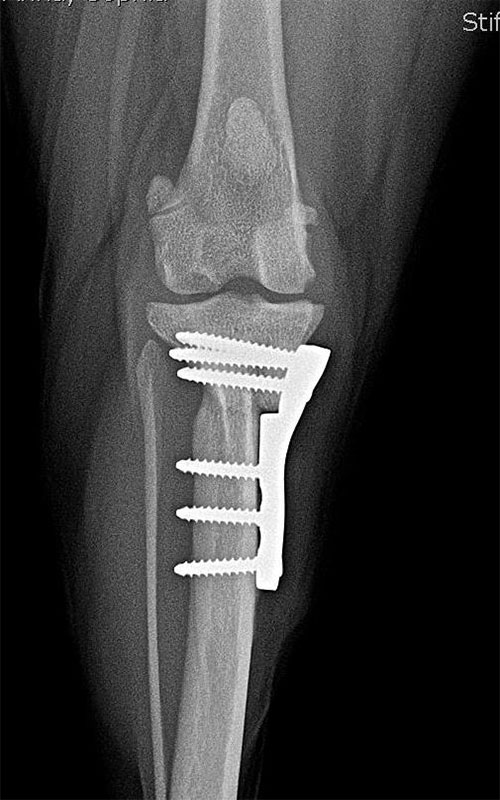

Update

The modification of TPLO is intended for the simultaneous correction of MPL and RACL. The new plate provides a high degree of stability and the polyaxiality gives the surgeon a high degree of freedom in choosing the direction of the screw insertion.

The picture shows a 2-month follow-up of the case in our previous post, with limp-free limb use and adequate bone healing.